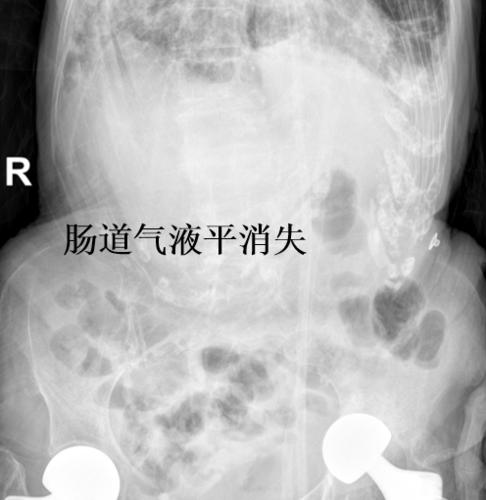

患者恢复了自主排气排便,复查x光片显示肠道的气液平完全消失,肠梗阻